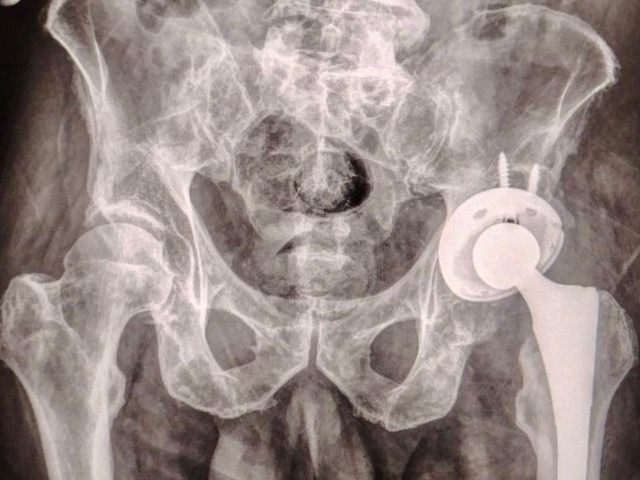

El Gobierno del Estado de Puebla a través del Instituto de Seguridad y Servicios Sociales de los Trabajadores al Servicio de los Poderes del Estado de Puebla (ISSSTEP), realizó con éxito y bienestar la colocación de la primera prótesis de cadera sin costo para el paciente. Esto representa un nuevo hito en el fortalecimiento de sus servicios médicos de alta especialidad.

La intervención quirúrgica fue realizada por un equipo multidisciplinario altamente capacitado, bajo estrictos protocolos de seguridad y criterios clínicos de selección. Este procedimiento representa un paso significativo en la atención integral de padecimientos osteoarticulares. Es especialmente importante para pacientes con desgaste articular severo que afecta su calidad de vida y movilidad.